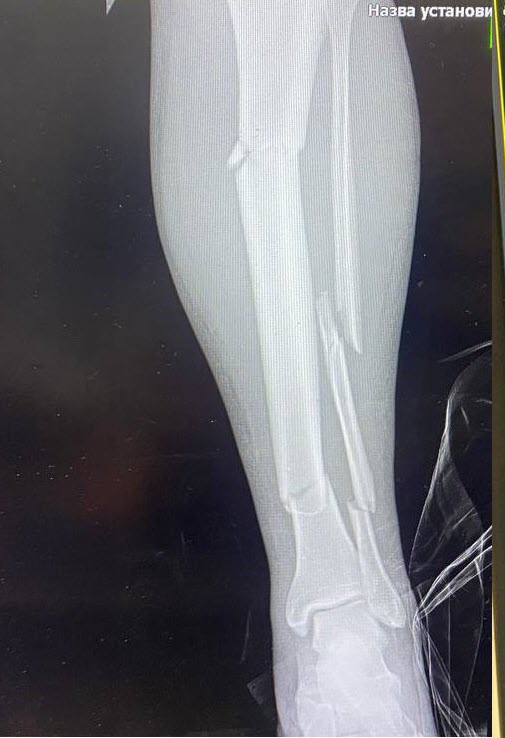

Він додає, що це було вкрай важке поранення, множинні переломи лівої ноги, розрив печінки та селезінки.

Воїну протягом п’ять годин в операційній збирали до купи фрагменти кісткових уламків.